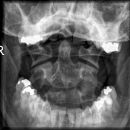

Dens (Spezialaufnahme)

Patient in Rückenlage, Körper gerade ausrichten, Prothesen usw. entfernen, 15° Keil unter den Kopf legen, Bissfläche der oberen Zahnreihe senkrecht über Hinterhaupt, Mund öffnen.

Senkrecht in den Mund, kleine Einblendung.

Bissebene und Unterkante des Hinterhaupts sollen sich überdecken. Der Dens ist mittelständig: gleicher Abstand zum aufsteigenden Ast des Unterkiefers beidseits. Weitgehend überlagerungsfreie Darstellung des Atlas und des Axis mit Dens. Gut einsehbares Atlantookzipital- und Atlantoaxialgelenk. Der vordere und der hintere Atlasbogen überlagern den Dens.